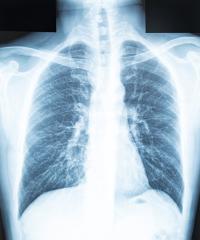

Provides diagnosis, treatment and case management for Orange County residents with tuberculosis (TB) disease. Provides TB screening services (TB testing, chest X-rays, symptom check, and physician evaluation, when appropriate) and treatment for latent TB infection for Orange County residents who are at highest risk for progression from TB infection to active TB disease. TB screening services are not offered to individuals needing work or school clearances, including but not limited to: students, teachers, school volunteers, certified employees (e.g., janitors), health care workers, childcare workers, and foster parents.